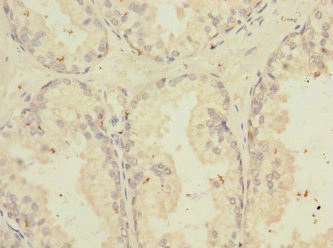

圖片:

應用范圍:ELISA, IHC

Application Recommended Dilution IHC 1:20-1:200 -